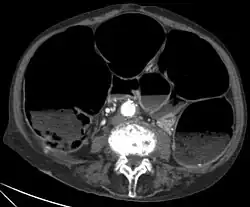

![]() Obraz pseudoniedrożności w badaniu CT | |

Zespół Ogilviego (ang. Ogilvie syndrome), ostra pseudoniedrożność okrężnicy (acute colonic pseudo-obstruction) – zespół objawów związanych z ostrym rozdęciem jelita grubego przy braku mechanicznej przeszkody powodującej jego niedrożność.

Rozpoznanie zespołu Ogilviego jest trudne i często opóźnione[1] ze względu na podobieństwo objawów do niedrożności mechanicznej i bardzo częste współistnienie innych, ciężkich chorób pacjenta. Podstawą rozpoznania jest stwierdzenie typowych objawów klinicznych oraz badanie radiologiczne (zdjęcie przeglądowe) wykazujące poszerzenie okrężnicy, często z poziomami płynów. Przy ocenie badania radiologicznego istotne znaczenie ma pomiar szerokości kątnicy ze względu na wybór sposobu dalszego postępowania i znaczenie rokownicze[9].

W rozpoznaniu różnicowym uwzględnia się niedrożność mechaniczną oraz ostre rozdęcie okrężnicy w przebiegu jej zapalenia rzekomobłoniastego. W przypadku wątpliwości co do przyczyny rozdęcia okrężnicy pomocne może być wykonanie badania tomograficznego lub sigmoidoskopii. Przy ocenie badań zwraca się szczególną uwagę na obecność objawów najgroźniejszych powikłań zespołu Ogilviego, jakimi są niedokrwienie jelita i jego perforacja.